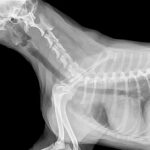

Poliuria quiere decir un aumento excesivo en la producción de orina durante varias veces al día. Debe distinguirse de la polaquiuria, que es la necesidad de orinar varias veces durante el día, pero con volúmenes normales o menores a lo normal.

Polidipsia es el aumento excesivo de ingesta de cantidades de agua superiores a las normales por parte de nuestra mascota. Esto se traduce en la constante sensación de sed que experimentan los perros. Estas dos condiciones también se dan (como la mayoría) en medicina humana.

Cuando aumenta la ingesta de agua, la volemia (cantidad de sangre) se incrementa y la osmolalidad de la sangre (solutos) disminuye. Esto resumidamente hace que aumente el volumen urinario. Aunque parezca controvertido, pueden presentar deshidratación, aunque esté aumentada la ingesta de agua.

Como antes explicábamos, ambos términos son signos o síntomas, no enfermedades en sí mismas. Además, cuando ocurre una, ocurre la otra, por lo que van de la mano. No obstante, siempre que se den hay una patología subyacente a la que están haciendo referencia. Algunas de estas patologías son:

- Diabetes Mellitus. Esta es una enfermedad del páncreas endocrino. Se caracteriza por una falta de producción y liberación total o parcial de insulina. Esto conduce a un estado de hiperglucemia crónico (es la insulina la que se encarga de introducir la glucosa de la sangre al interior de las células y hacerla así funcional. Existen la tipo I: ausencia total de insulina) y la tipo II: hay insulina pero hay una resistencia a su acción.

El aumento de glucosa en el filtrado del riñón arrastra agua en la orina, aumentando así la producción de la misma. Por este motivo aparece la poliuria y polidipsia cuando se padece diabetes mellitus. - Síndrome de Cushing o hiperadrenocorticismo. Existe el hiperadrenocorticismo adrenal y el hipofisiario. Básicamente se traduce en un exceso anómalo de producción de corticoides (cortisol) en el cuerpo, produciendo diversos síntomas entre los que destacan la polidipsia poliuria. Se debe a que el exceso de cortisol aumenta el filtrado glomerular. Esto se da en el 80-90% de casos de síndrome de Cushing, incluido en gatos.

- Piómetra. La piómetra se denomina a la infección del útero la cual se da en hembras no castradas (uno de los motivos para realizar dicha intervención). Puede ser cerrada (el contenido no sale de la vagina al exterior) o abierta (observaremos secreciones). Suele producirse por la bacteria Escherichia coli. Uno de los múltiples síntomas que pueden aparecer es la polidipsia poliuria, posiblemente iniciado por la ascensión de dicha bacteria a desde el tracto reproductor a los riñones.